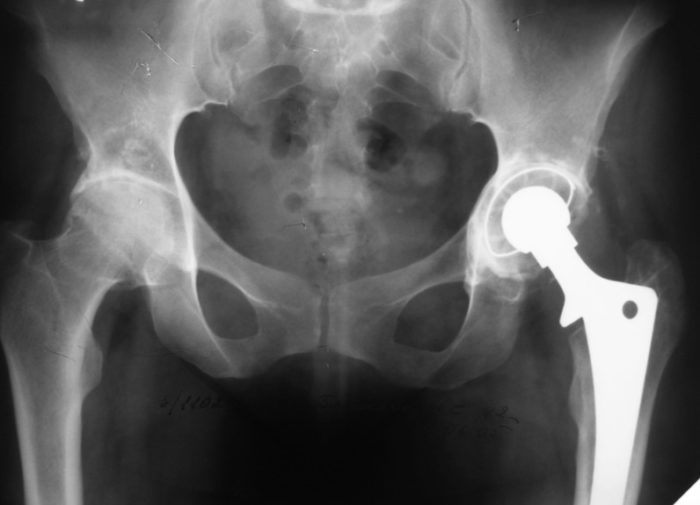

Также проводится осмотр пациента терапевтом и выполнение электрокардиограммы. Для выбора подходящего размера эндопротеза специалист выполняет рентгенографию тазобедренного сустава, а при необходимости — компьютерную томографию. После консультации с анестезиологом определяется оптимальная методика обезболивания: специальная анестезия или общий наркоз. Подготовка и обследование могут занять до пяти дней.